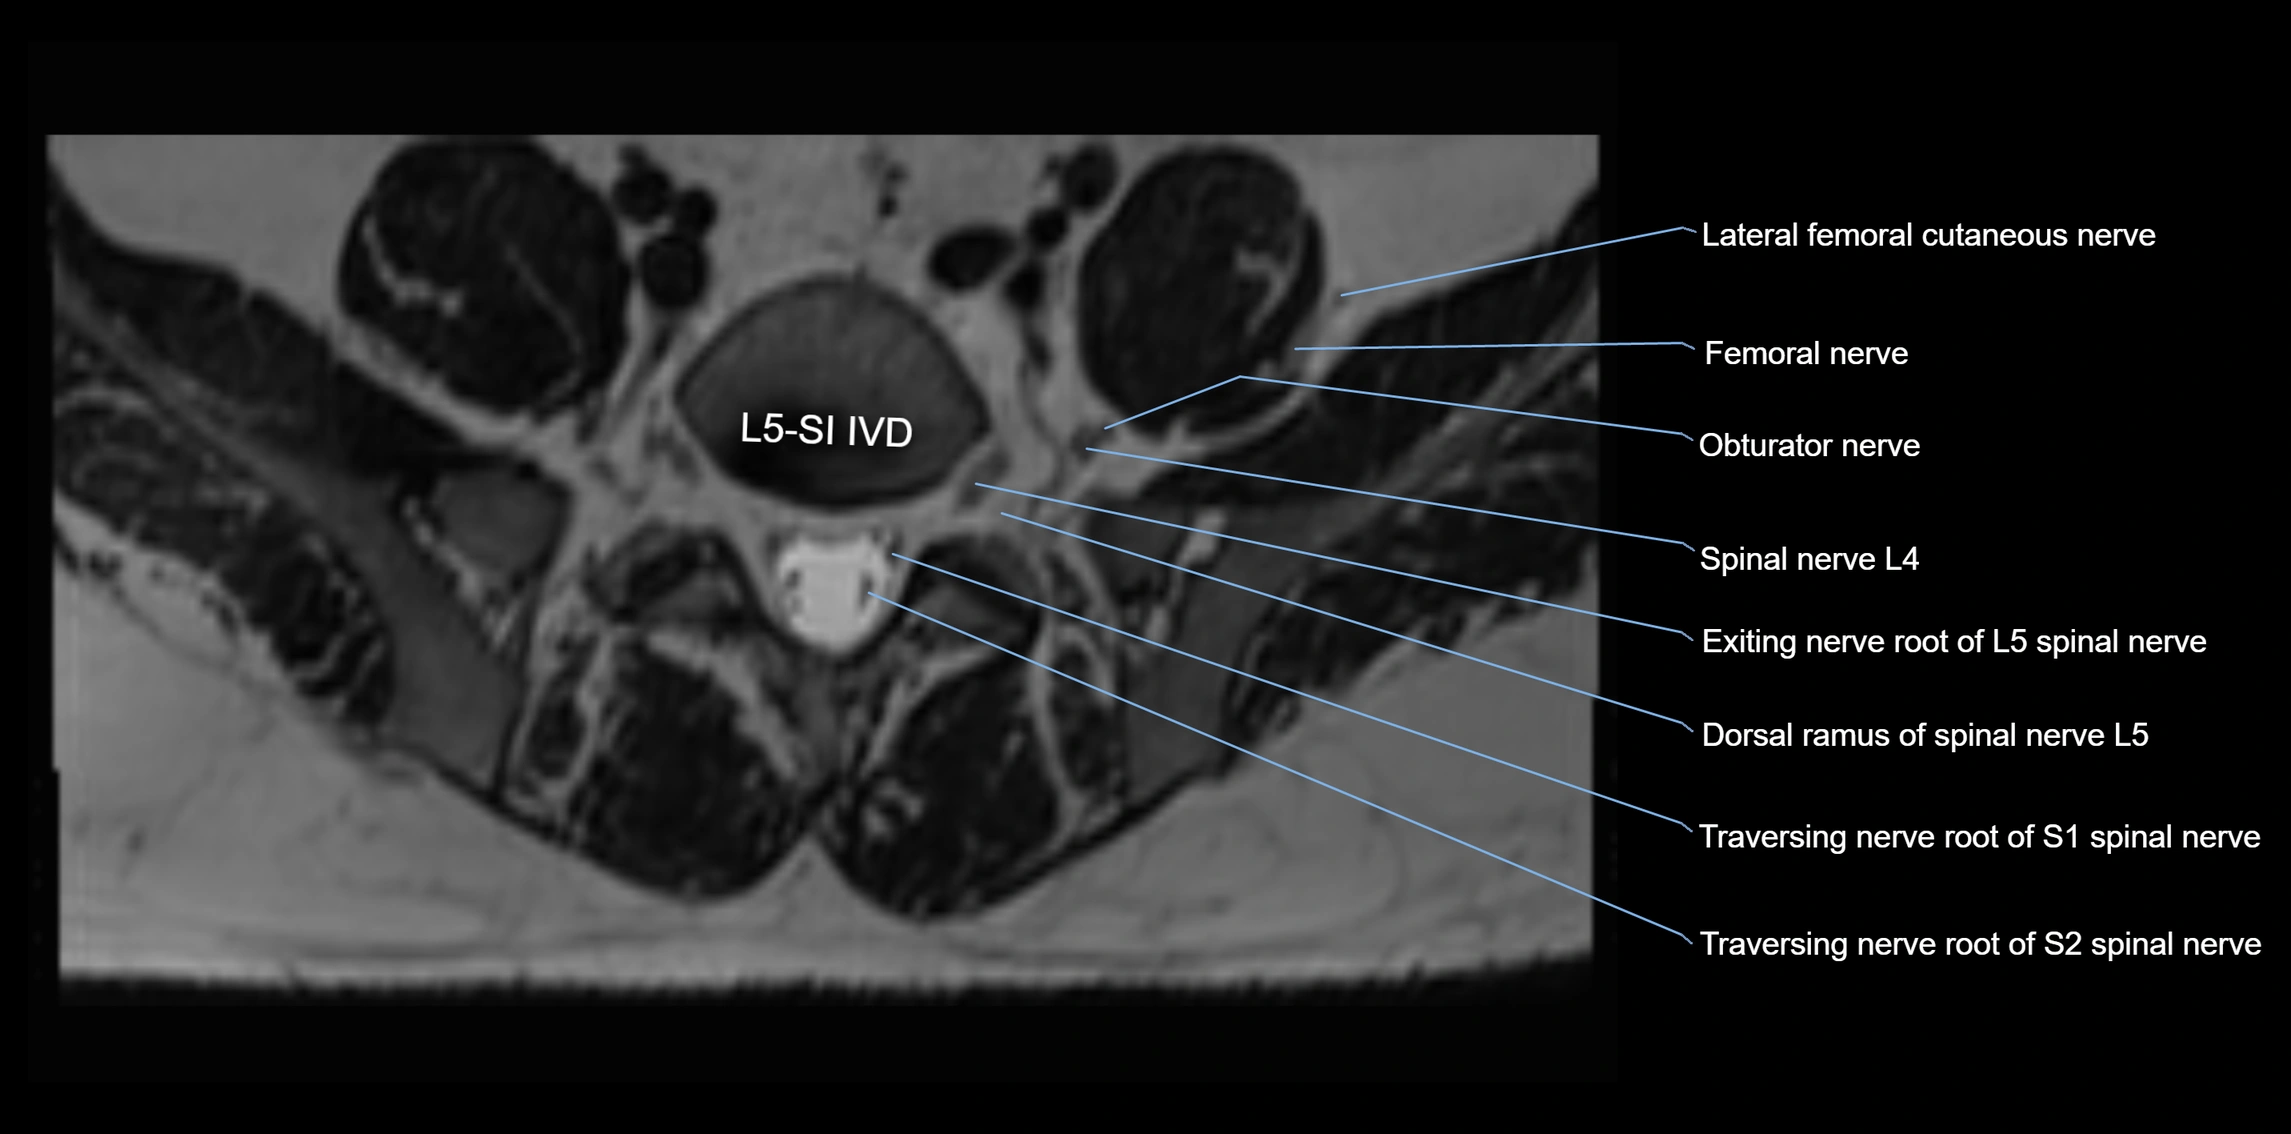

MRI Appearance

T1-weighted images:

• Nerve appears as a very thin low-to-intermediate signal intensity structure

• Surrounded by bright fat, aiding visualization

T2-weighted images:

• Nerve shows intermediate to mildly hyperintense signal compared to muscle

• Pathological involvement appears brighter

STIR (Short Tau Inversion Recovery):

• Normal nerve appears dark

• Inflamed or entrapped nerve appears bright hyperintense

T1 Fat-Sat Post-Contrast:

• Normal nerve enhances minimally

• Pathologic nerve (neuritis, entrapment, tumor infiltration) shows focal or diffuse enhancement

3D T2 SPACE / CISS:

• Nerve appears intermediate to mildly hyperintense compared to muscle

• Surrounded by bright fat or CSF, improving visualization

• Best sequence for mapping small pelvic nerves such as the anococcygeal